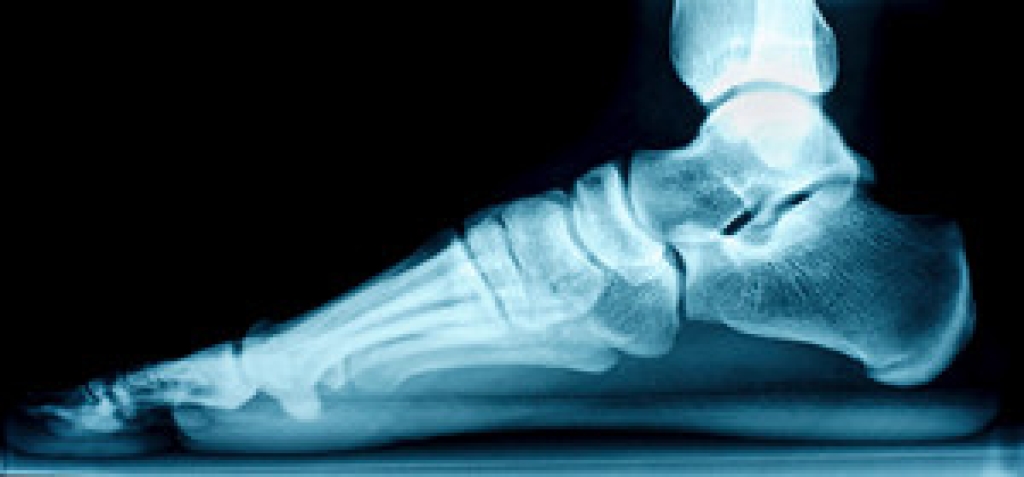

Gout is a form of arthritis that is characterized by sudden, severe attacks of pain, redness, and tenderness in the joints. The condition usually affects the joint at the base of the big toe. A gout attack can occur at any random time, such as the middle of the night while you are asleep.